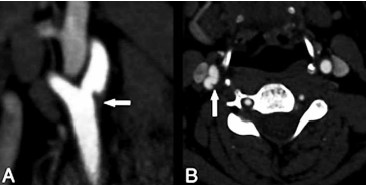

Paciente do sexo masculino, 45 anos de idade, procura o serviço de neurologia com quadro caracterizado por heminegligência, hemianopsia esquerda, parestesia no dimidio esquerda. Referiu que, 4 meses antes desse episódio, apresentou um quadro de dor cervical e dormência do lado esquerdo, com resolução espontânea em 1 dia e negou antecedentes de hipertensão arterial, diabetes e cardiopatias. Ecocardiograma e ECG seriado normais; provas reumatológicas negativas. Realizado uma tomografia e angiotomografia, que são apresentadas a seguir.

Considerando esses elementos, qual seria a sua principal hipótese diagnóstica?